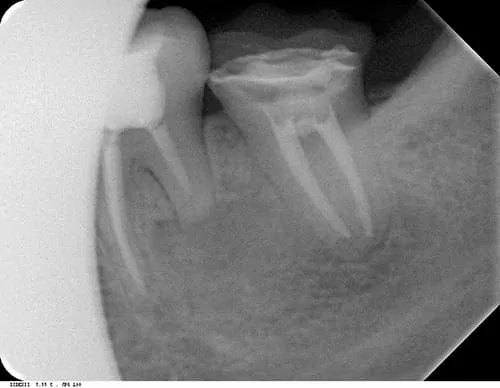

(2) 根尖X光片

根管治療術中 (左下第一大臼齒)

根管治療術後封填

根管治療術後三個月